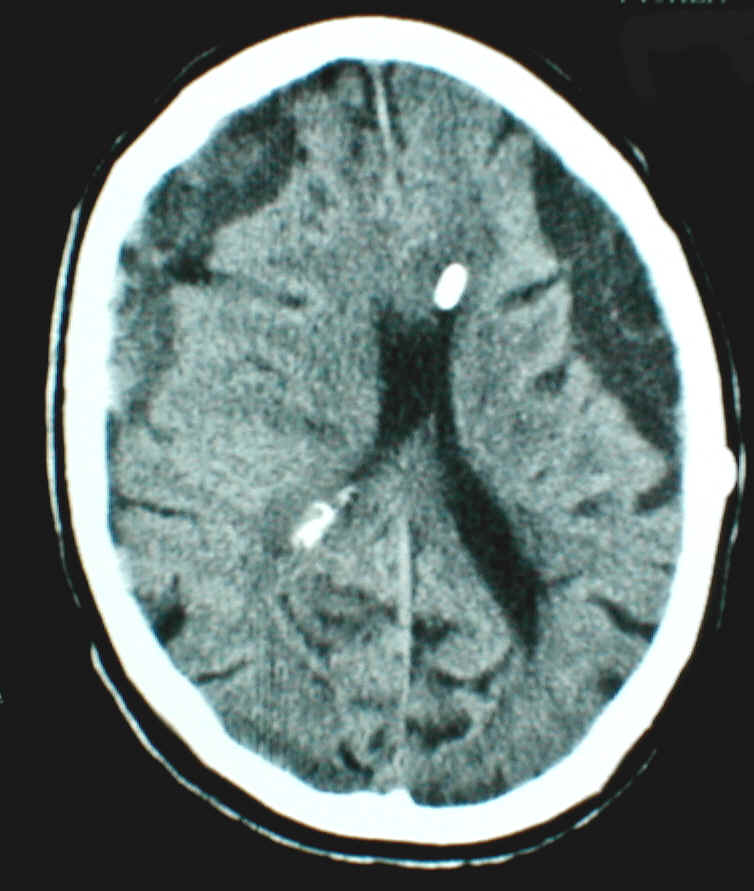

wie unter 4. Slit ventricle Syndrom erwähnt, kann es im Rahmen einer chronischen Überdrainage zum Verstopfen des Ventrikelkatheters kommen. Das Bild unten zeigt eine solche Komplikation. Unschwer erkennt man auf dem CT (rechts) die schlitzförmigen Ventrikel und dass der Ventrikelkatheter praktisch vollständig von Hirngewebe umschlossen ist. Die Folge ist auf dem linken Bild deutlich zu sehen. Die Löcher des Katheters und auch weitere Anteile des Shunts sind mit Gewebe verstopft. Dieser Shunt kann nicht mehr funktionieren.